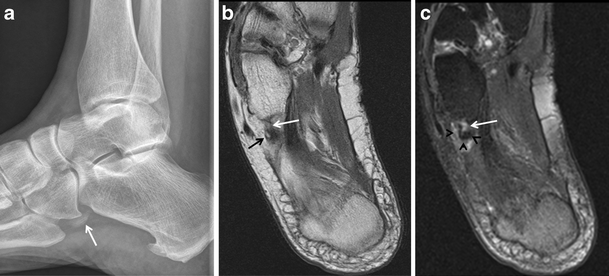

Os trigonum syndrome. a Lateral radiograph of the ankle demonstrates an os trigonum (arrow) and posterior soft-tissue prominence and infiltration of the pre-Achilles fat (arrowheads). Sagittal T1-weighted (b) and STIR (c) MRIs show bone marrow oedema (arrows) in the os trigonum, posterior recess nodularity and thickening (arrowheads), and a joint effusion (asterisk). The patient was a runner with clinical posterior impingement